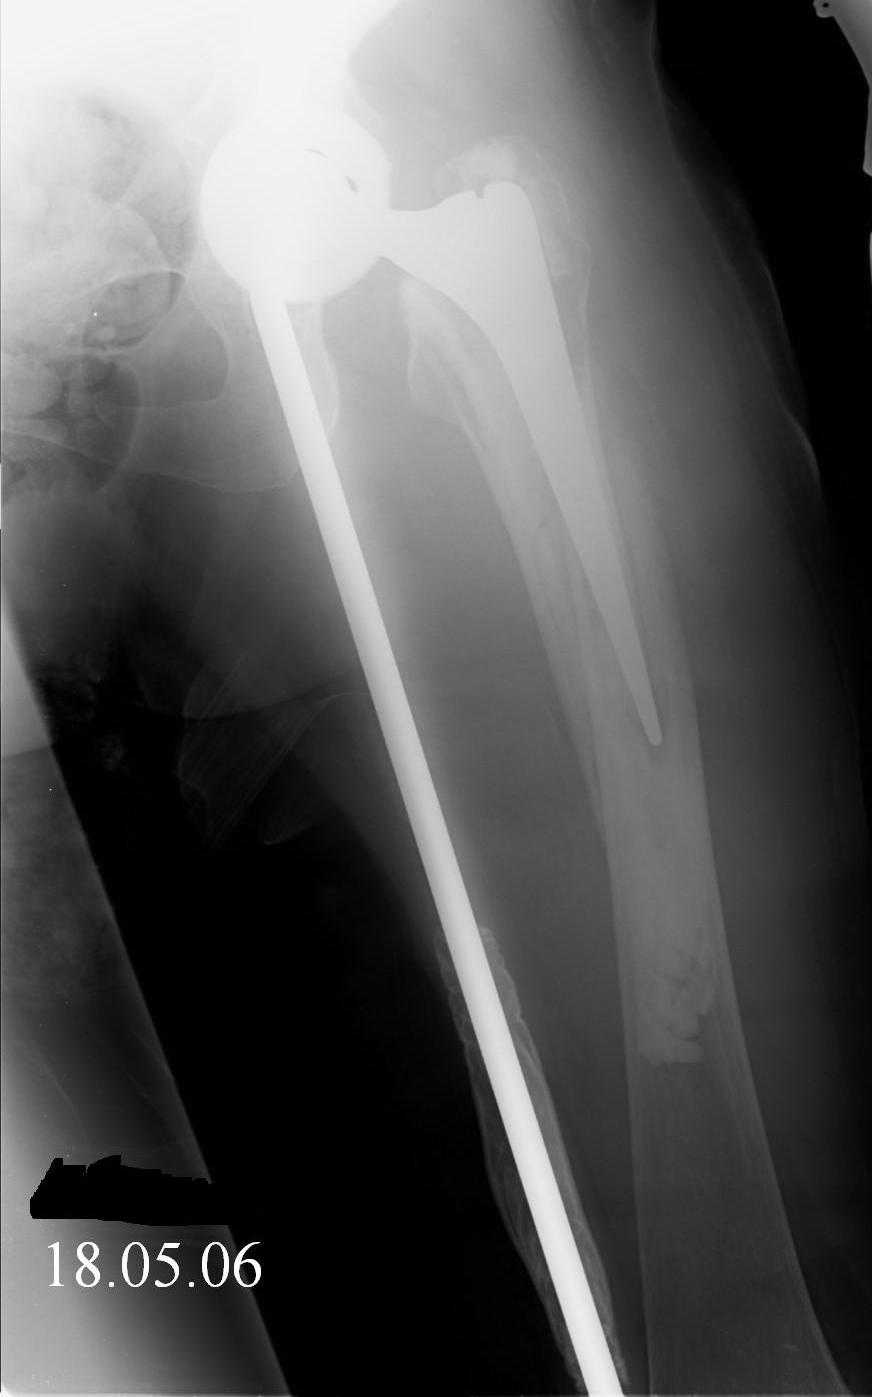

Reminded me of a case I did a couple years ago - 30 year old woman with juvenile rheumatoid arthritis and a nonunion below her stem. Fixed with retrograde nail which docked with the stem and a lateral locking plate. Image attached. One of the companies should come up with a stem design and nail system that anticipates this need.

Jeff Anglen, M.D.